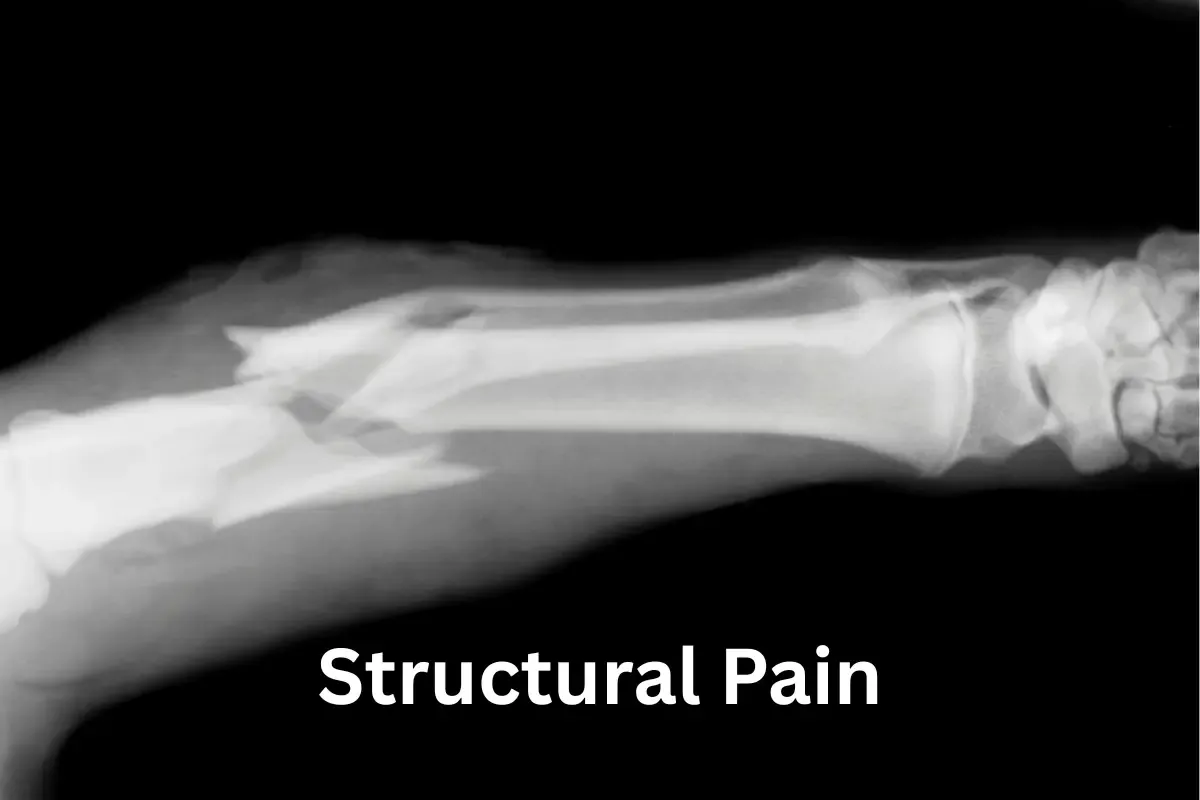

So, what exactly is this therapy that caught my attention? Basically, Pain Reprocessing Therapy (PRT) is a way of retraining your brain to read your body’s signals correctly. It is essential to note that this is for pain that persists after an injury has healed, or where no structural cause can be found.